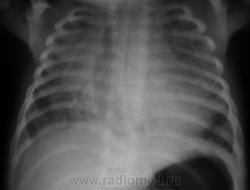

Двустороннее тотальное снижение прозрачности обоих легочных полей - одна из форм пневмопатии новорожденных и недоношенных, скорее всего синдром/болезнь гиалиновых мембран.

Воздух в средостении?

Я поставил двустороннюю пневмонию и , вы абсолютно правы Валентин Львович-есть воздух в средостении . У ребёнка множественные пороки развития -в т.ч. атрезия одной из хоан . Мама сама устанавливала назогастральный зонд-вывод напрашиваетя сам(проткнула пищевод)

Как-то очень сомнительно, что она смогла это проделать, зонд же гибкий, эластичный.

Как верифицирован случай? Я разделяю скепсис Шиба: при перфорации пищевода был бы медиастенит, по картине скорее, можно преположть аноалию трахеобронхиального дерева, в виде трахеомегалии.

Согласен насчет пневмонии, или РДС-синдрома. Про перфорацию - ну не знаю, хотя всякие неожиданные картинки нам жизнь подкидывает. Если снимок в горизонтальном положении (газовый пузырь желудка не видно...) - скорее, пневмоторакс справа.